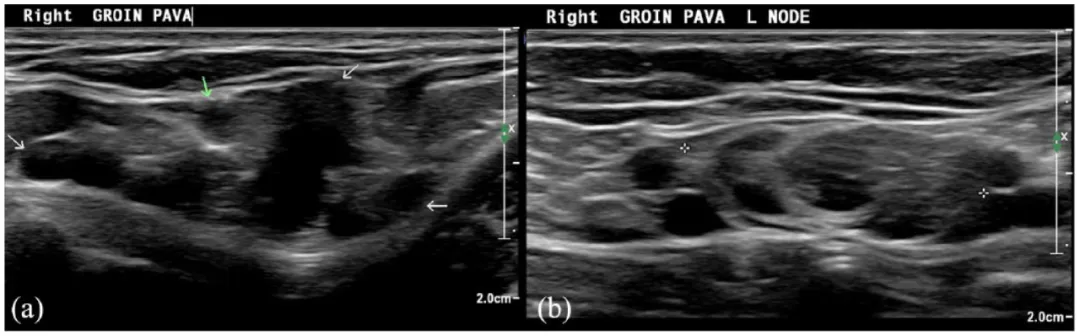

如果通过导管给药,而不是从单点向上静脉注射UGFS,会更成功,并且在静脉周围注射肿胀液,增加硬化剂的停留时间。然而,这降低了手术的简单性,使手术过程与EVTA相似,但结果较差。积极的一面是,对于小直径和薄壁静脉,如小静脉曲张和网状静脉,新生血管组织,剥除处血管再生和原发性瓣膜静脉畸形(PAVA)组织,UGFS是目前的最佳治疗方法。静脉切除术在这些静脉中大多数是不合适的,他们太小和浅表也不适合EVTA。

图:(a)静脉超声显示右腹股沟隐筋膜内的原发性瓣膜静脉曲张畸形(PAVA)组织- 大隐静脉 (GSV) 和前副隐静脉 (AASV) 先前消融-箭头显示不同的PAVA血管。(b)同一患者显示PAVA进出一个淋巴结。